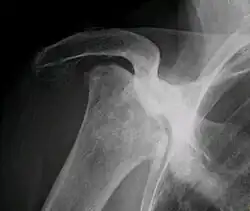

Radiografia de necrose total avascular da cabeça do úmero direita. Mulher de 81 anos de idade com diabetes de longa duração